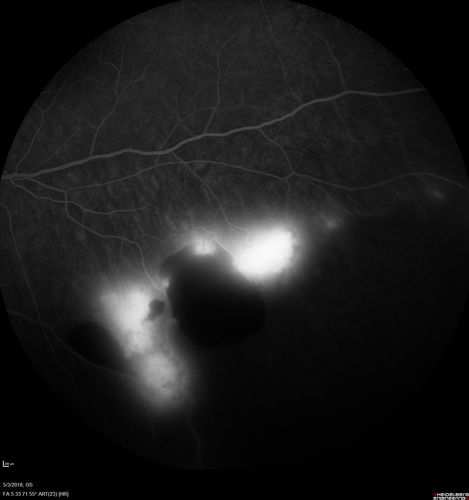

Coats' Disease -51 year old asymptomatic male

20/20 vision - had laser to non-perfusion because of proliferation.